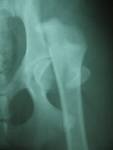

Epifisiólisis de la cabeza femoral. Se trata del desplazamiento del núcleo epifisario en relación con el cuello del fémur, generalmente progresivo, en un cartílago casi siempre al final de su crecimiento (que señala el envejecimiento prematuro del cartílago).

Epifisiólisis aguda. El desplazamiento epifisario tiene lugar en pacientes cuyos síntomas datan de menos de 3 semanas. Muchas veces, su inicio es brusco, con un dolor intenso asociado o no a un traumatismo previo. En las radiografías no se observan signos de remodelación en la zona metafisaria del cuello femoral.

Deslizamiento agudo sobre crónico. Los síntomas datan de menos de 3 semanas, pero existen signos radiográficos de remodelamiento metafisario en el cuello femoral. Es, por tanto, un deslizamiento agudo sobre otro crónico ya existente.

Deslizamiento crónico. Es el tipo más frecuente. La aparición de los síntomas data de más de 3 semanas, existiendo además fenómenos de remodelación y pudiendo estar la epífisis cerrada. En general, existe una historia de varios meses de evolución con los síntomas, pero van empeorando de forma paulatina a medida que progresa el deslizamiento. Puesto que la continuidad entre el cuello femoral y la epífisis de la cabeza del fémur se mantiene, los síntomas no son intensos y el niño puede caminar con una marcha ligeramente antiálgica en rotación externa.